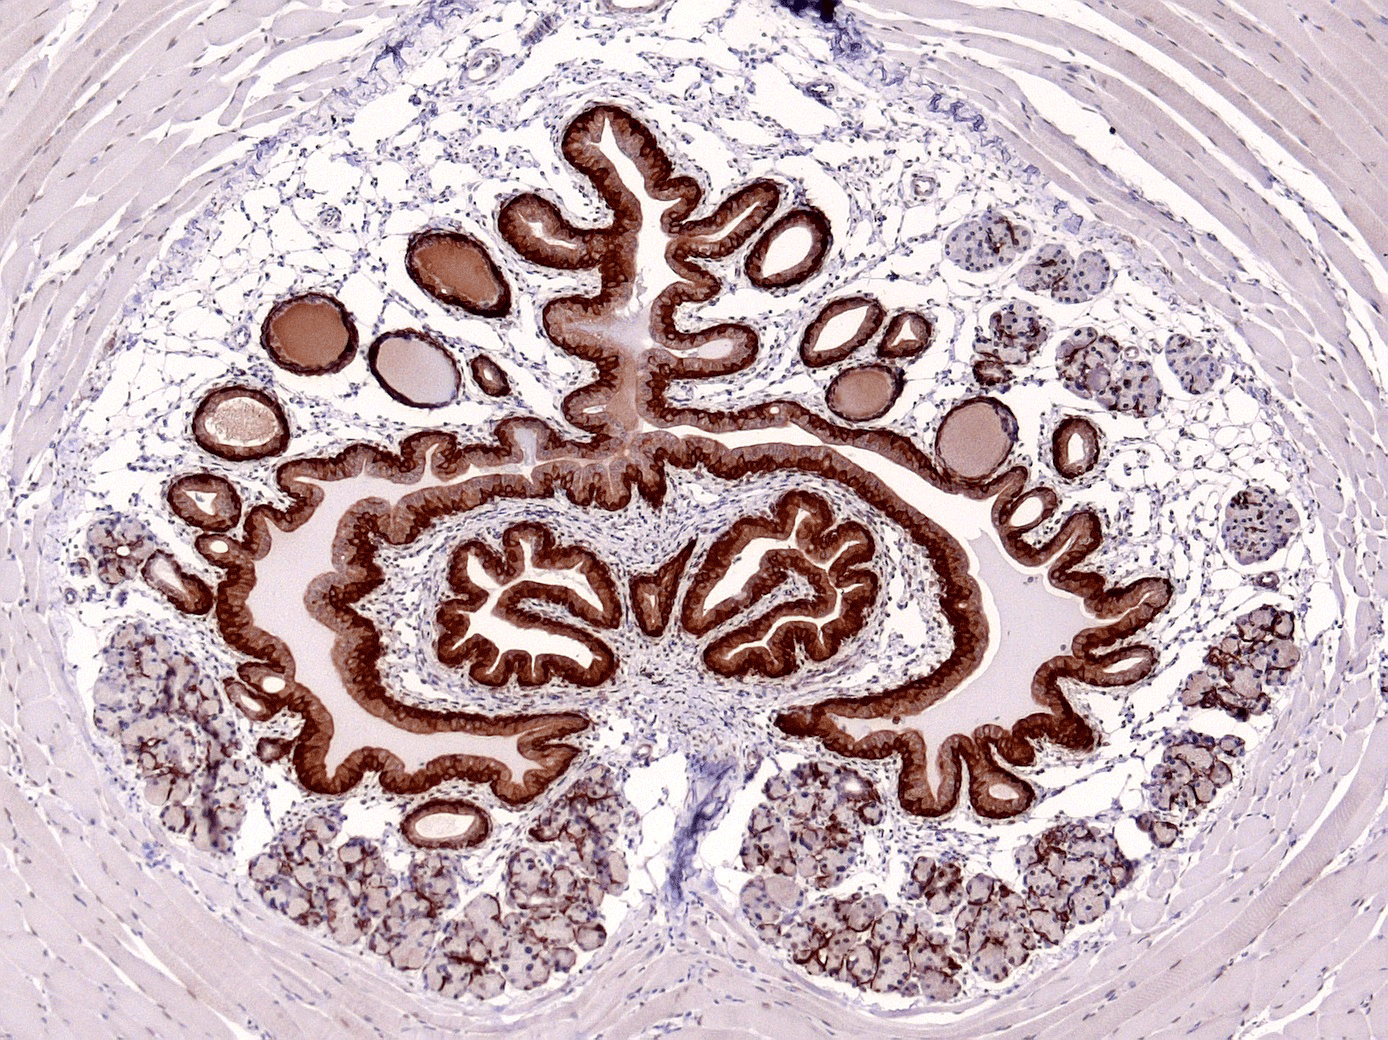

Edgar Büttner - BIOTEC - Utethra

The image shows a urethra acquired with brightfield microscopy, supported by LMF CRTD/BIOTEC